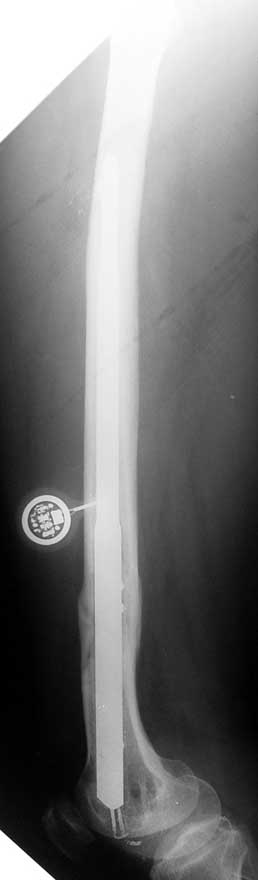

Case 1